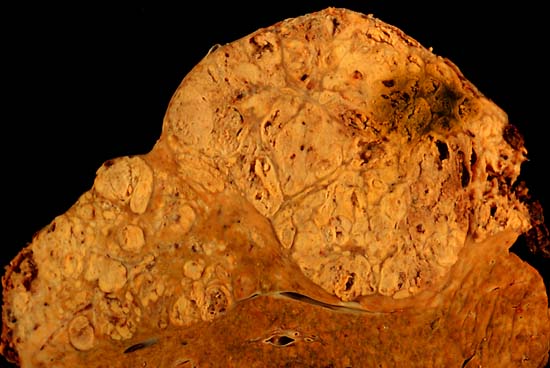

Hepatocellular carcinoma This specimen is from a 50ish woman who presented to the hospital with abdominal pain and ascites. The radiologist recovered what appeared to be whole blood on paracentesis. Cytological exam of the bloody fluid showed no evidence of malignancy. Liver function tests were abnormal, and serologic tests were positive for antibody to hepatitis C. The patient deteriorated rapidly and died within a few days. The autopsy showed this hepatocellular carcinoma occupying much of the volume of a cirrhotic liver. Furthermore, the tumor had invaded the diaphragm and ruptured into the peritoneal cavity, causing the bloody ascites. The photo shows a view of a longitudinal slice taken through the full length of the liver. The photos were shot with a Minolta X-370 with 100mm bellows lens on Kodak Elite ISO 100 transparency film. The specimen was sliced fresh and fixed in formalin overnight, then briefly immersed in 70% alcohol to retrieve some of the native colour and dull the surface reflections. Photograph by Ed Uthman, MD. Public domain. Posted 23 Sep 00 |